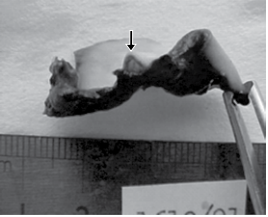

A figura a seguir corresponde à realização da Docimásia Hidrostática de Galeno durante uma necropsia de feto para a constatação se houve vida extra-uterina.

Observa-se que fragmentos dos pulmões flutuam no recipiente contendo água. Pode-se afirmar, portanto, que